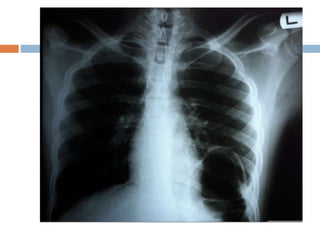

 The initial chest radiograph performed in

the ED was interpreted as showing a

loculated air trapping on base of left

hemithorax.

To identify the definite cause of the matter,

CT-Imaging of the abdomen with oral and Iv

contrast was performed which demonstrated

left diaphragmatic rupture with herniation of

viscus into the left hemithorax